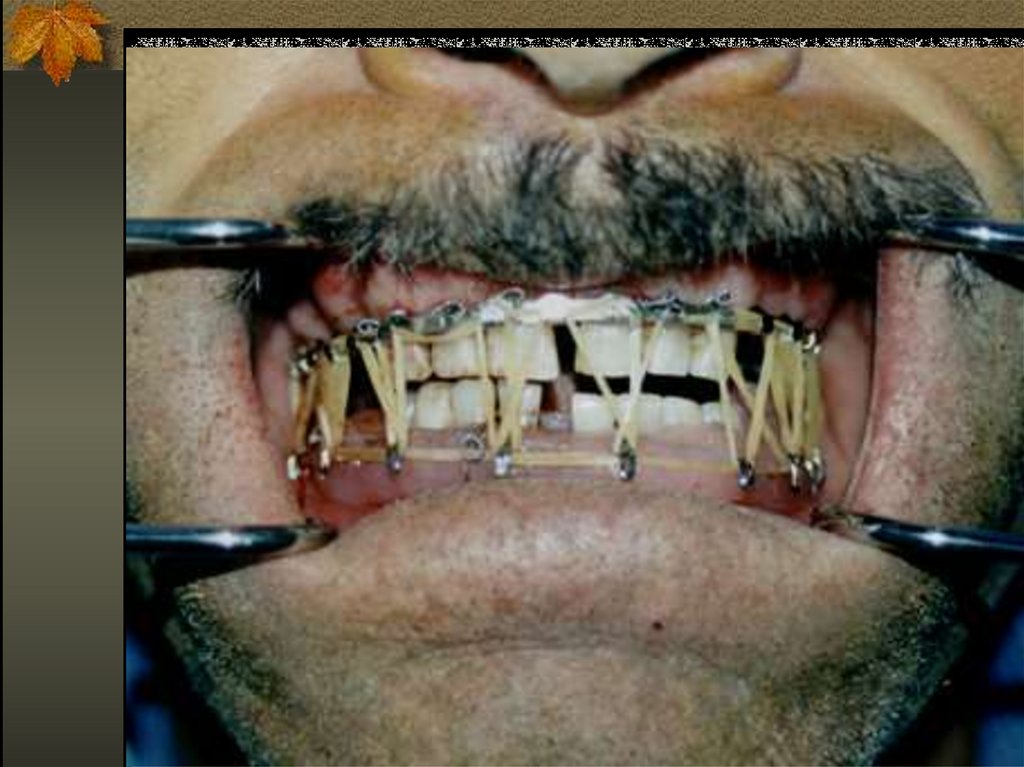

Ligatürler iki amaçla yapılır.

1- ligatüre tatbik edilen kauçuk halkaların

yardımı ile alt ve üst diş kavisleri

arasında bir çekme göreci ile

redüksiyonu sağlar.

2- üst diş kavisleriyle alt diş kavislerinin

tellerle tespiti ile kontansiyonu sağlar.